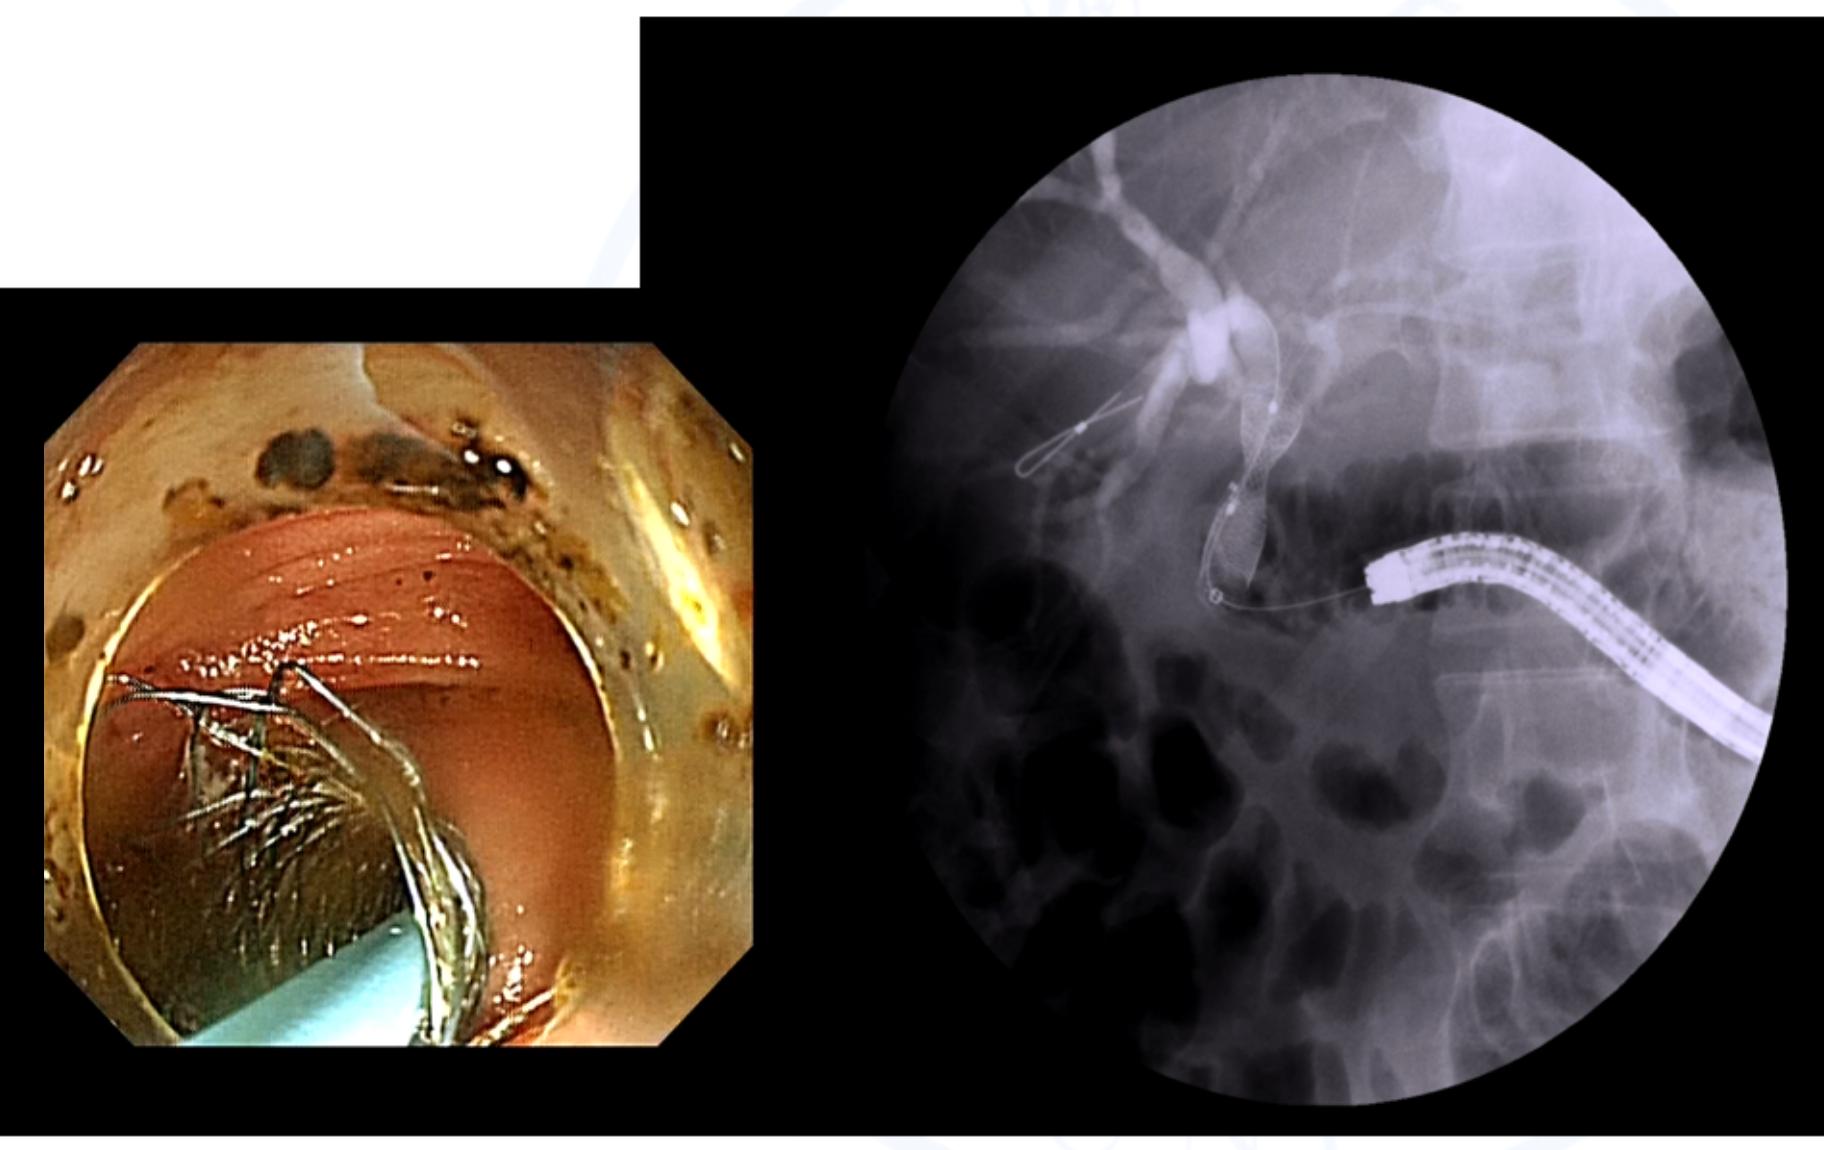

值得注意的是,胆肠吻合口狭窄患者常合并较多肝内胆管结石,在结石未有效清除前胆道镜不能直接到达胆肠吻合口,不能及时、有效地对胆肠吻合口狭窄进行扩张治疗。另有部分胆肠吻合口狭窄患者的肝内胆管扩张并不明显,导致穿刺困难无法行PTCS术;或者部分患者虽穿刺成功,但胆道镜无法有效到达狭窄的胆肠吻合口。而ERCP技术的发展,使这部分患者免于再次手术治疗。内镜到达吻合口后,可对吻合口进行球囊扩张,植入胆道内引流管并进行取石操作。对于吻合口炎性或瘢痕狭窄的患者,也可植入金属支架,对狭窄进行缓慢而持续的扩张6-12月,有利于防治吻合口扩张后的再次狭窄。

综上所述,对于胆肠吻合术后吻合口狭窄的治疗,再次手术不再是病人治疗的惟一手段,PTCS及ERCP同样能达到一定疗效。虽然目前此项诊治技术在国内外并未完全普及,一方面受限于较高的操作技术要求,另一方面缺乏相关与之配套的操作器械,但随着内镜诊治技术逐步发展,将会有越来越多的胆肠吻合术后病人从中受益。